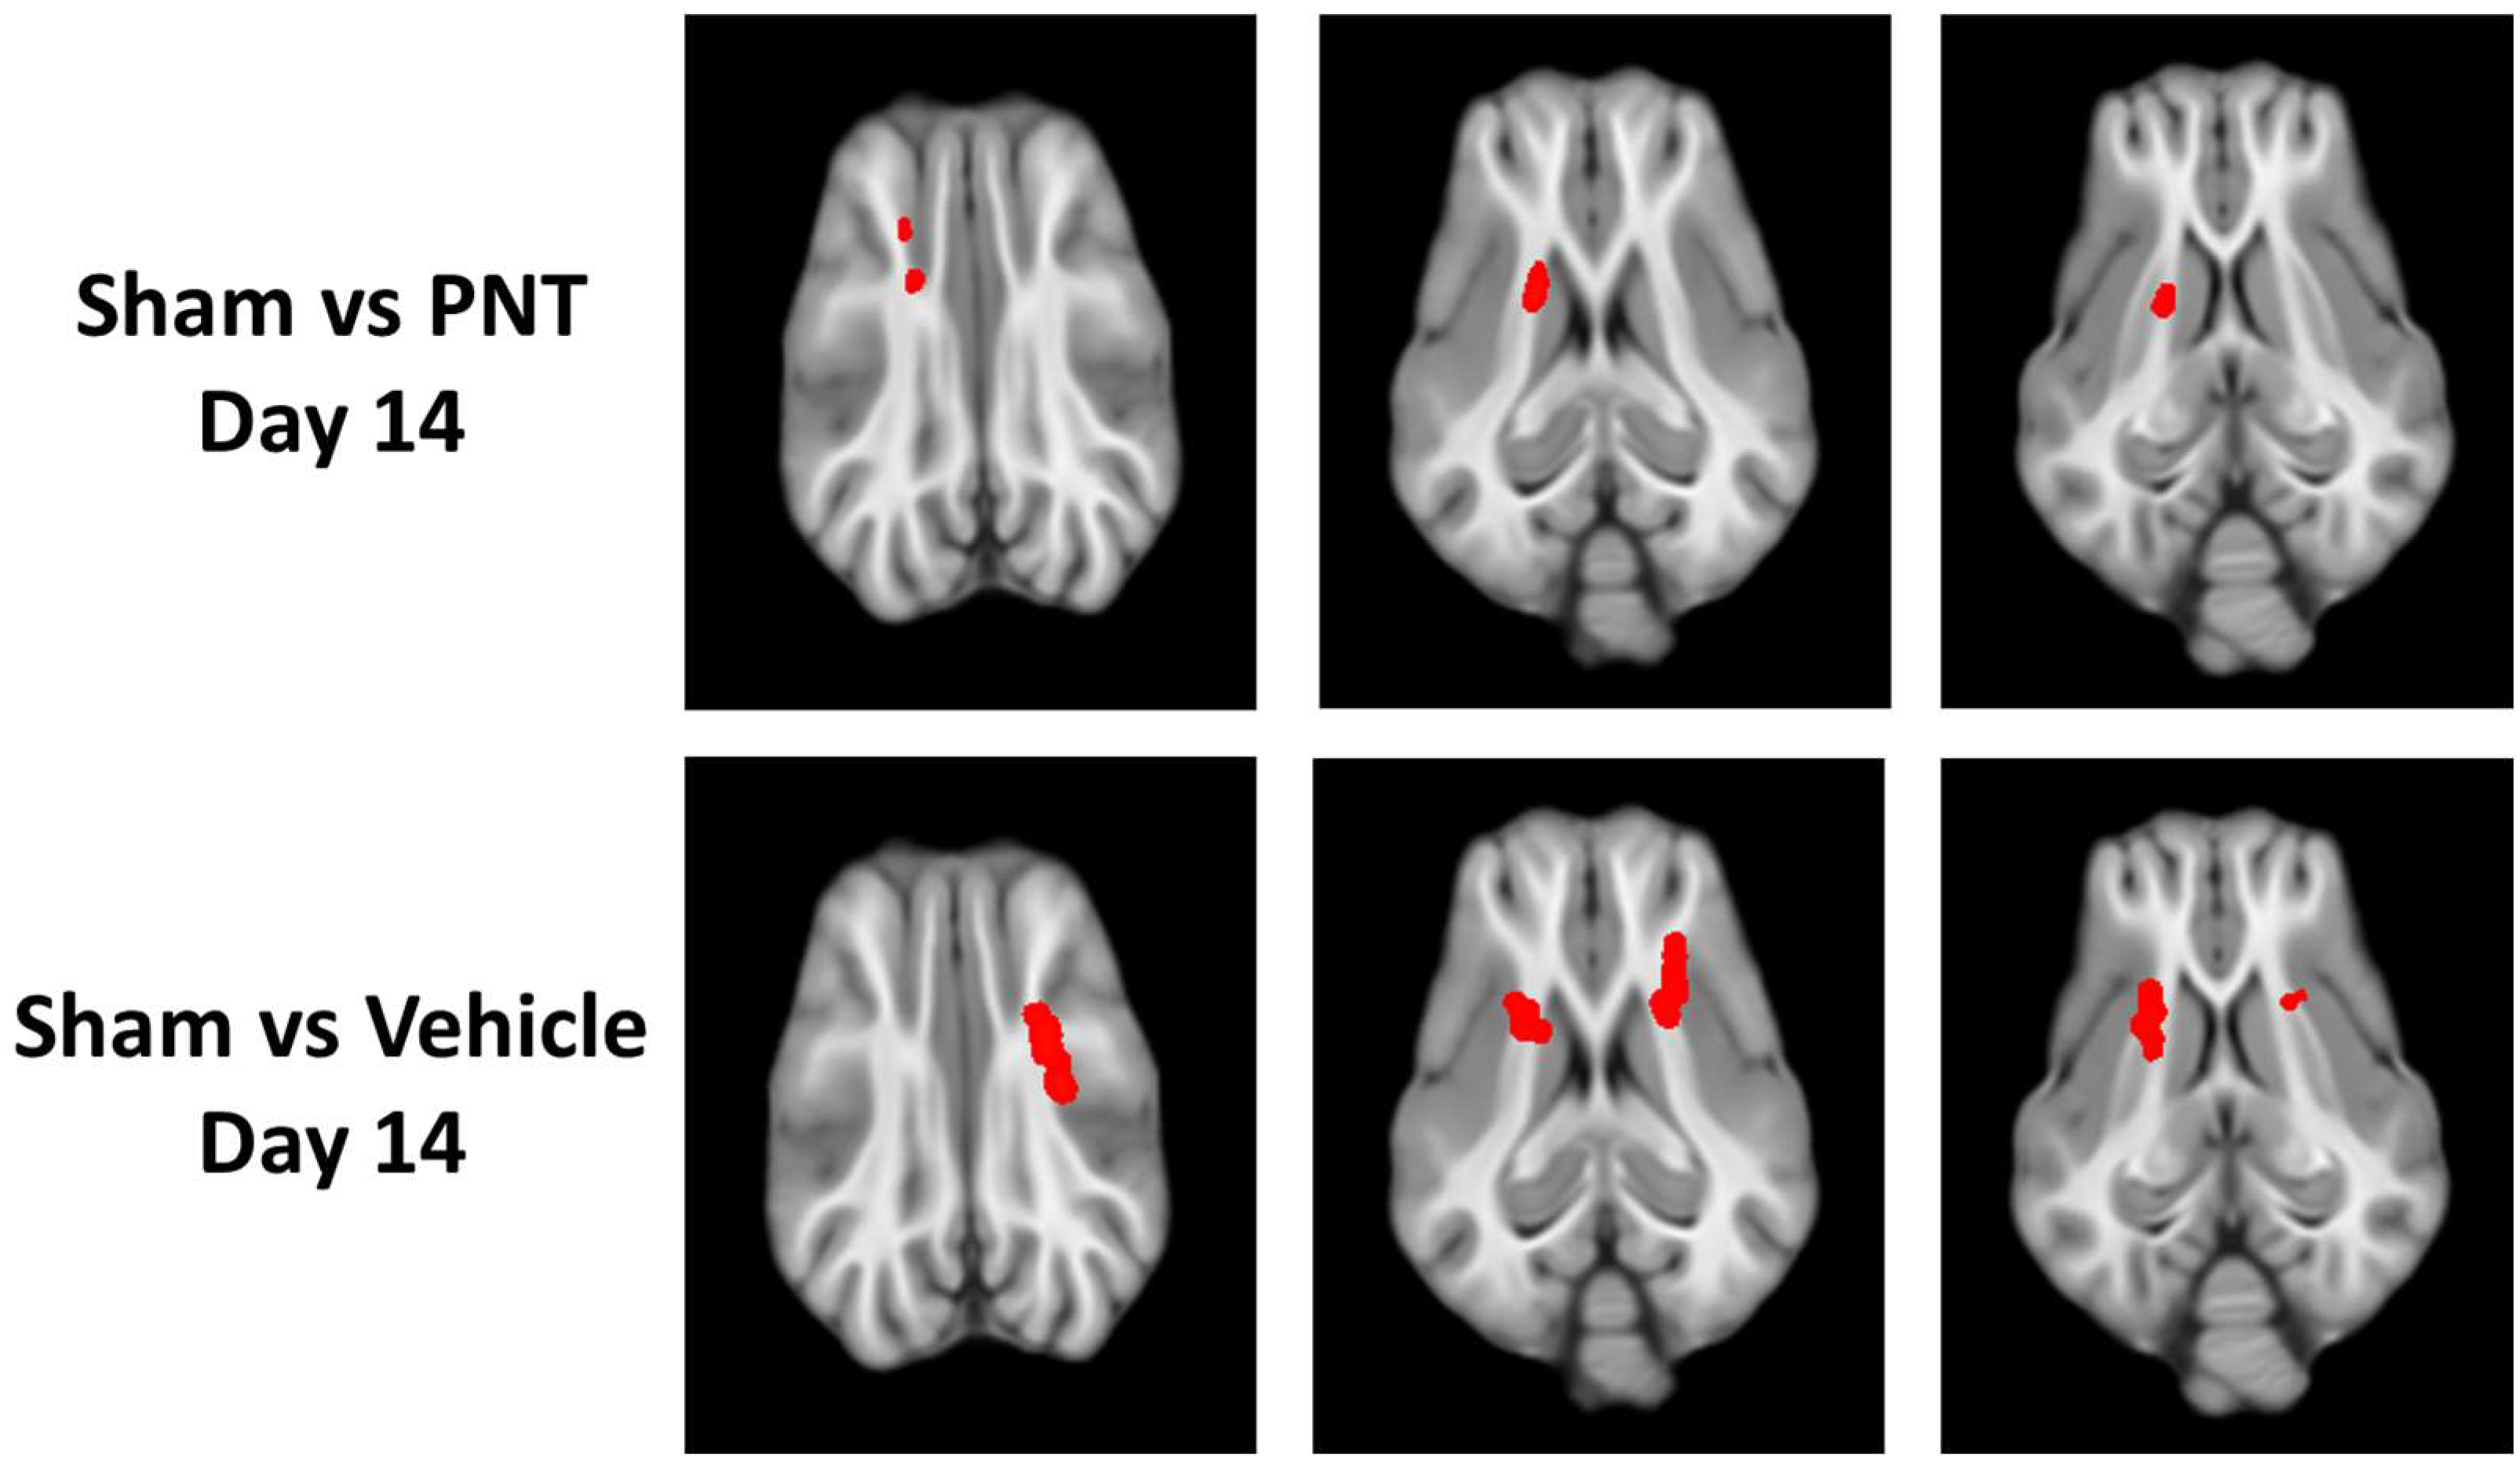

After the administration of the vehicle or PNT001(60 mg/kg, intravenous), we analyzed drug exposure in an initial subset of eight animals in both serum and CSF to validate the appropriate administration (Figure S1). This showed the appropriate drug levels in the serum and CSF of the pigs, which were in agreement with the previously demonstrated Kd of PNT [10]. Then, we analyzed the time course of white matter integrity using DTI at 1 day and 14 days. At 1 day following TBI, there were multiple areas of significant reduction in FA among both the PNT001- and vehicle-treated CCI pigs (Figure 2). Both the PNT001-treated and vehicle-treated injured animals exhibited reduced FA levels in the corona radiata. Whereas the PNT001-treated animals appeared to have smaller areas of FA reduction in the bilateral corona radiata, the vehicle-treated group appeared to have larger areas of FA reduction. Specifically, the contralateral (left) corona radiata and posterior portion of the corpus callosum showed an FA reduction.

For the quantification of the white matter integrity, we normalized the FA values to our historical sham animals’ FA levels in each respective area, as shown in (Figure 3). In agreement with the heat map of the areas with FA reduction (Figure 2), there was a significant decrease in the FA values of the corona radiata for both the vehicle- and PNT001-treated groups compared to the sham pigs. The PNT001-treated pigs also displayed a reduction in the MD in the corpus callosum, while the vehicle-treated group did not. When DTI was performed again at the 14-day time point (Figure 4), there were significant reductions in the areas in which FA decreases were acutely observed. The quantification of the reductions in the FA in these regions at 14 days resulted in significant differences between the sham and vehicle groups but not the sham and PNT001 groups at the right corona radiata (Figure 5). Although the heat map showed small areas of FA reduction in the bilateral corona radiata, because the region of FA reduction was very small, the quantitative assessment showed no significant difference between the sham and vehicle or PNT001 groups in the left corona radiata. Similarly, the longitudinal study using linear mixed effects model showed no significant differences between the two groups for FA and MD (Table S1).

In the DTI scans of pigs following TBI, specific areas of FA reduction were found in the bilateral corona radiata and splenium of the corpus callosum. These areas of injury were consistent with our previously reported DTI data on 30-day post-injury pigs [16], indicating the selective vulnerability of these regions to TBI. Changes in FA levels at the ipsilateral corona radiata were specifically correlated with rises in both NFL and GFAP also in this study, supporting the validity of these radiographical findings. Although the quantification of FA values at each location showed no significant differences between the vehicle-treated and PNT001-treated groups, the subtle differences in the size of the area with FA changes between the two groups was more clear in the heat maps. These data showed that while there was no major effect in reducing the white matter damage by PNT001, the subtle reduction, as shown by heat map, may indicate that optimal dose and administration times should be explored. Over the 14 days, the areas of FA reduction were significantly attenuated, as shown between Figure 2 and Figure 4. This change may be partly due to the recovery process of white matter injury over time, but decreasing tissue edema may also account for this, as previously noted [16].

Figure 2. FA map showing difference between sham vs PNT-treated CCI group (top) and sham vs vehicle-treated CCI group (bottom) at 1 day following injury. The red–yellow regions show FA-reduced areas as compared to sham group.

Figure 4. FA map showing difference between sham vs PNT001-treated CCI group (top) and sham vs vehicle-treated CCI group (bottom) at 14 days. The red regions show FA-reduced areas as compared to sham group. PNT = PNT001.